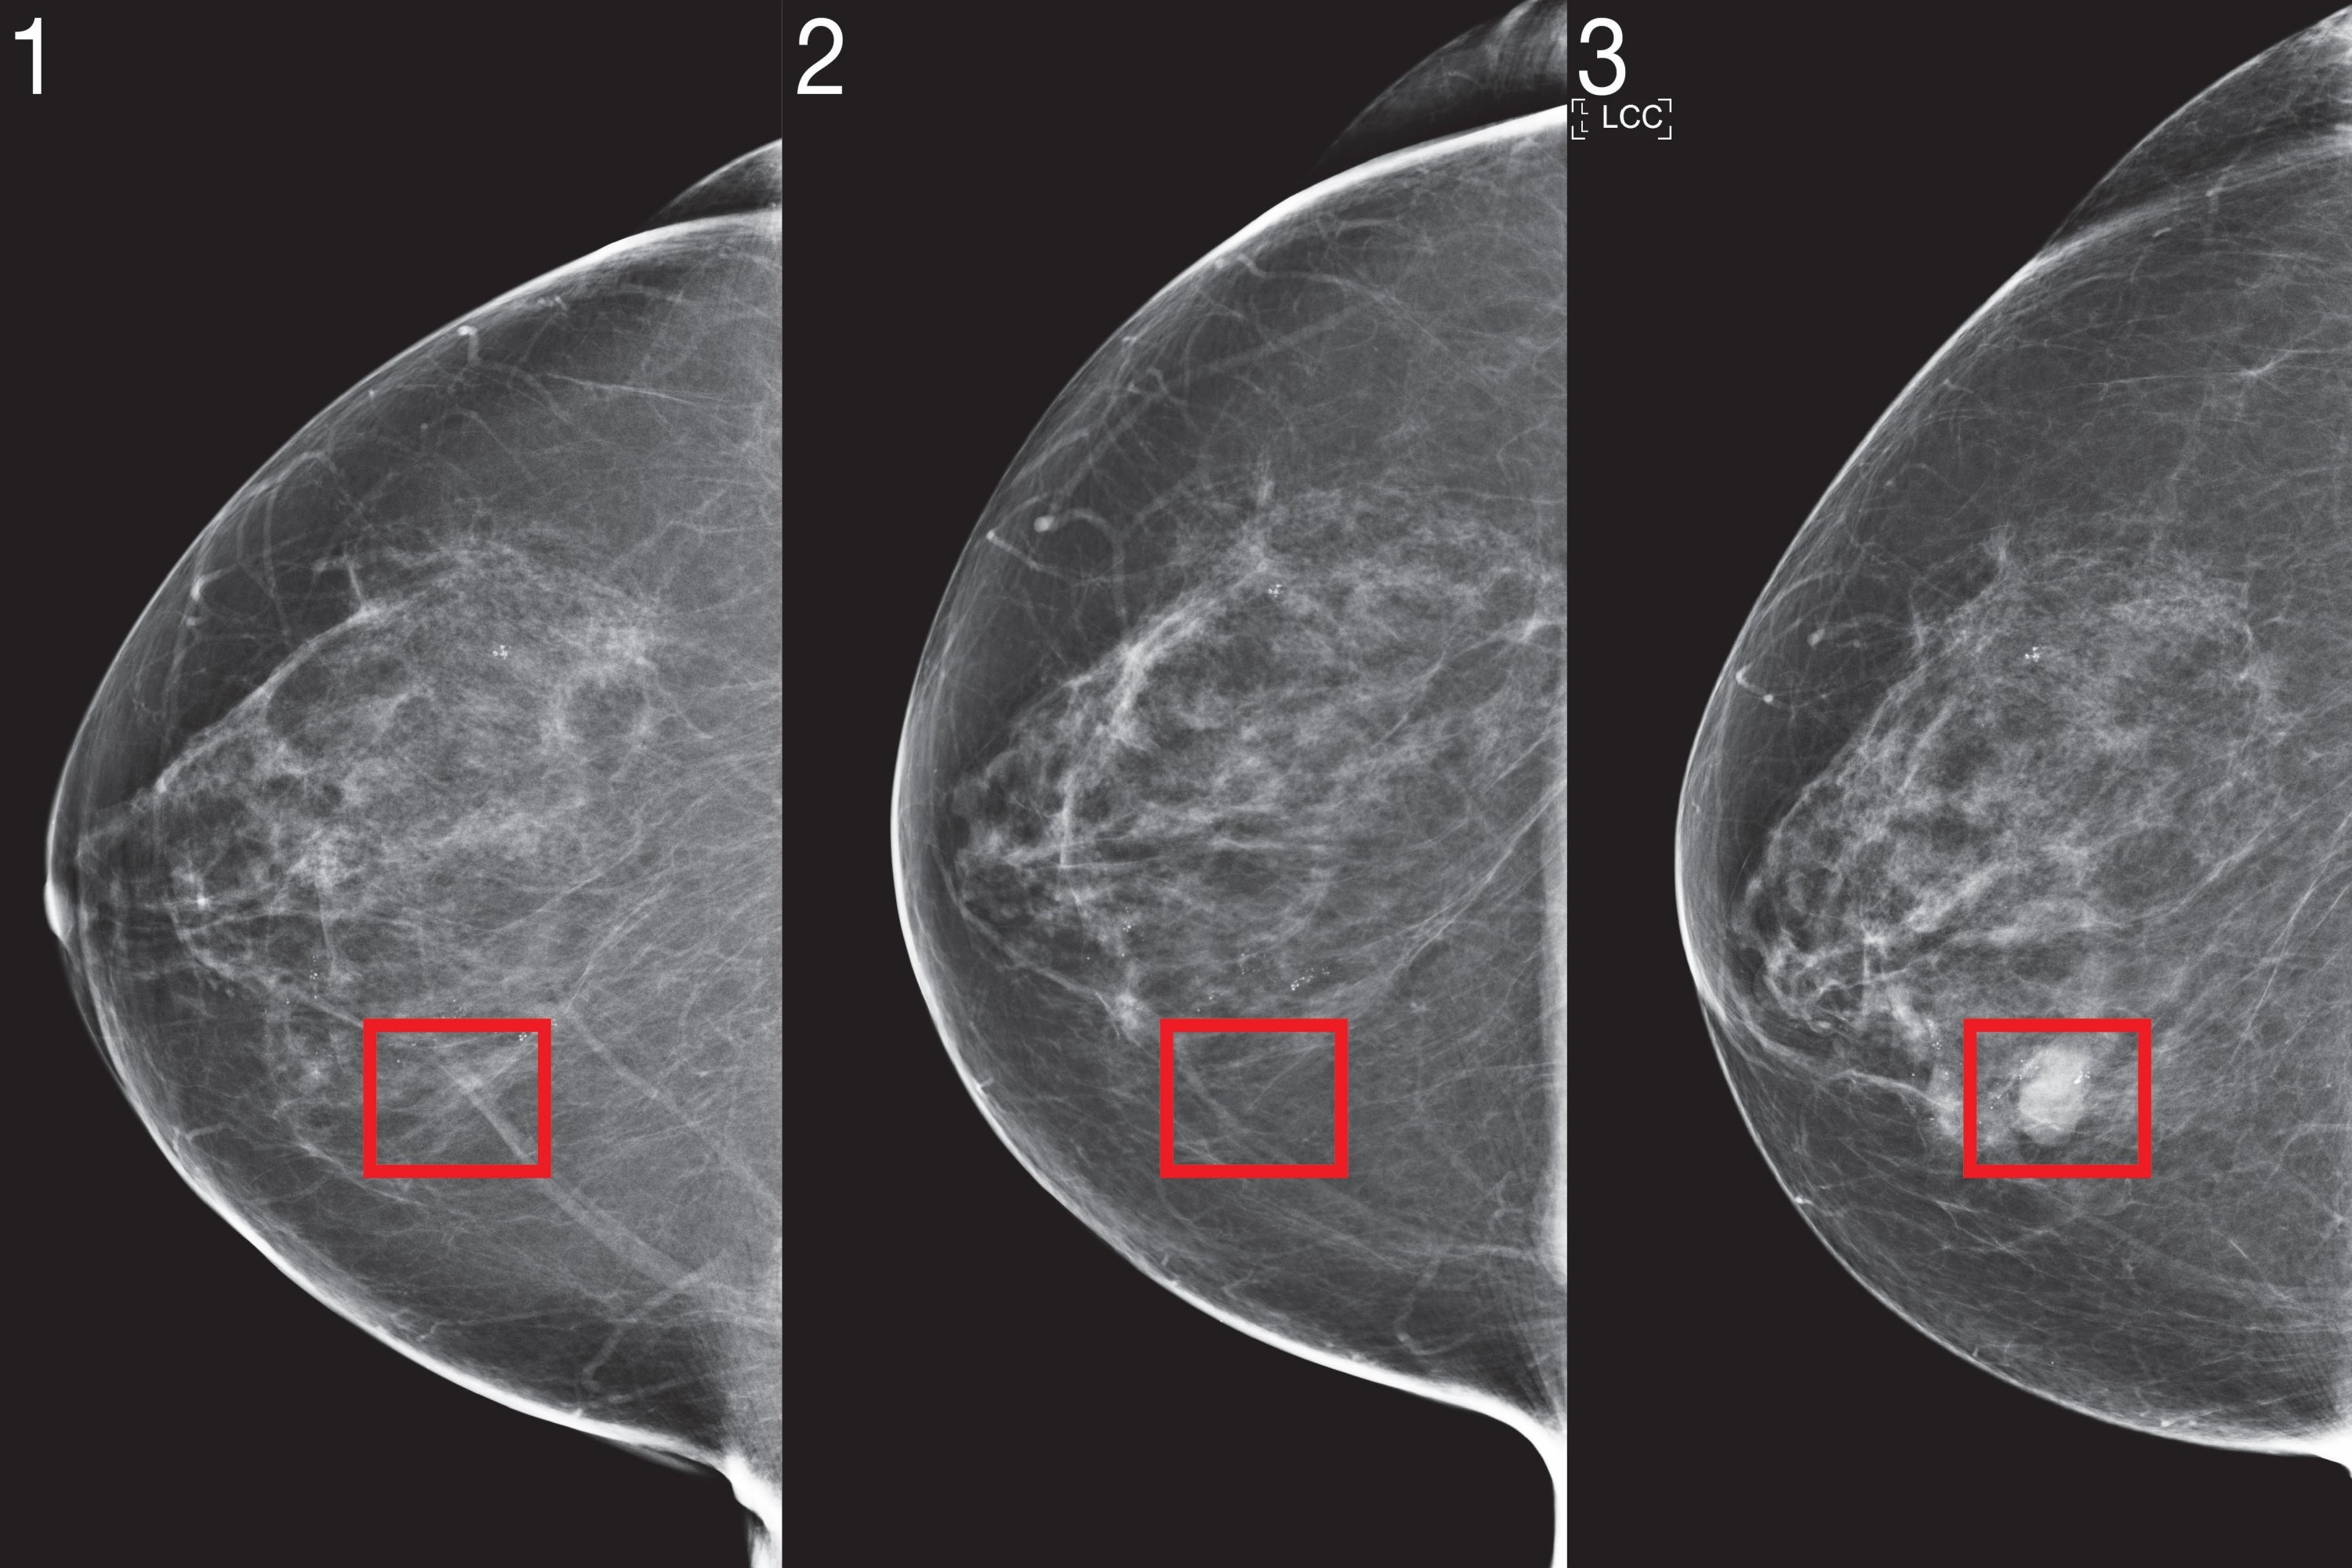

Recently, deep learning mammography-based risk models have shown promising performance. To bring this technology to the clinic, the team identified three innovations they believe are critical for risk modeling: jointly modeling time, the optional use of non-image risk factors, and methods to ensure consistent performance across clinical settings.

Although the current model doesn’t look at any of the patient’s previous imaging results, changes in imaging over time contain a wealth of information. In the future the team aims to create methods that can effectively utilize a patient’s full imaging history.

In a similar fashion, the team notes that the model could be further improved by utilizing “tomosynthesis,” an X-ray technique for screening asymptomatic cancer patients. Beyond improving accuracy, additional research is required to determine how to adapt image-based risk models to different mammography devices with limited data.